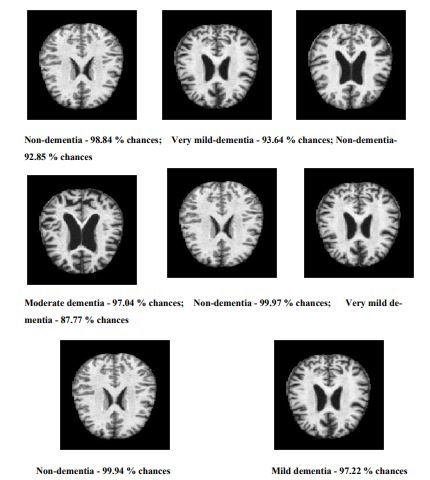

The various samples applied to detect and classify the various stages of Alzheimer’s disease using the proposed Sequential CNN are shown in Fig. (5).

All the various stages, like dementia, non-dementia, moderate dementia, and very mild dementia, can classify with a minimum of 88.6% validation. The performance of the proposed method is compared with the existing methods, and it is tabulated in Table 6.